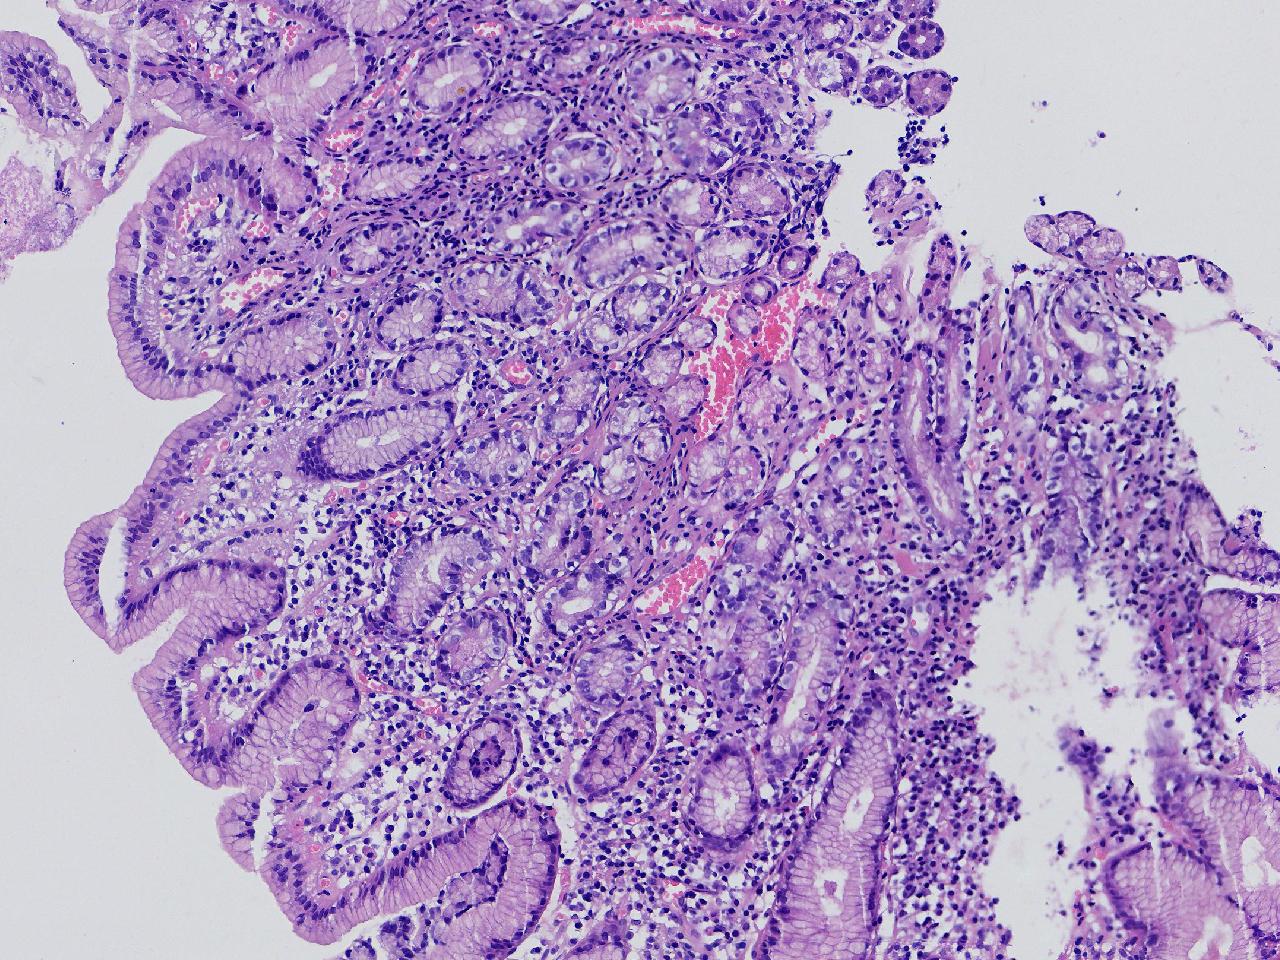

间质内是炎细胞吗?

男,49岁,胃镜活检,胃窦粘膜红白相间,以红为主,后壁见一直径约0.4cm大小片平隆起,表面糜烂,活检1块送检,质软弹性可。

胃窦活检

灰白色不整形软组织1块,直径0.2厘米。

是!还有组织细胞

幽门型粘膜中度慢性炎

是的,主要是淋巴细胞和浆细胞。